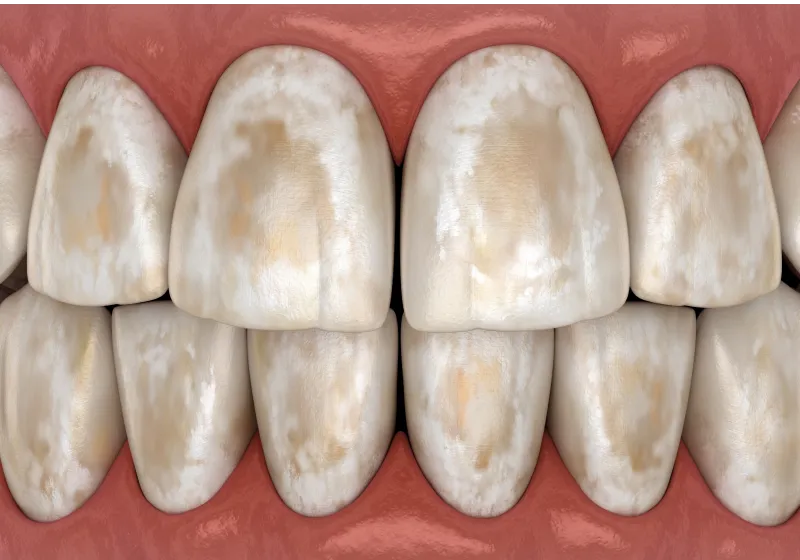

歯間の「黒い隙間」を修復|

40代 女性

歯間乳頭再建による審美性と機能性の回復

治療名 【高度審美形成】歯間乳頭再建術 治療期間 約1年 執刀医 Dr. 大杉 治療費 300,000円(税込) 治療解説 ブラックトライアングルに対し、歯を削ったり抜いたりせずに形態改善を目指して歯間乳頭再建術を行いました。

上顎口蓋から採取した結合組織を歯間部へ移植し、マイクロスコープ下で精密に縫合。

審美面の改善に加え、食渣(食べかす)が詰まりにくい状態の回復を目指しました。リスク・副作用 移植組織の定着後も、メンテナンスが予後を大きく左右します。

特に歯間ブラシの不適切な使用や過度なブラッシング圧は組織の退縮を招くため、術後は当院の指導に基づいた厳密なプラークコントロールが必要です。